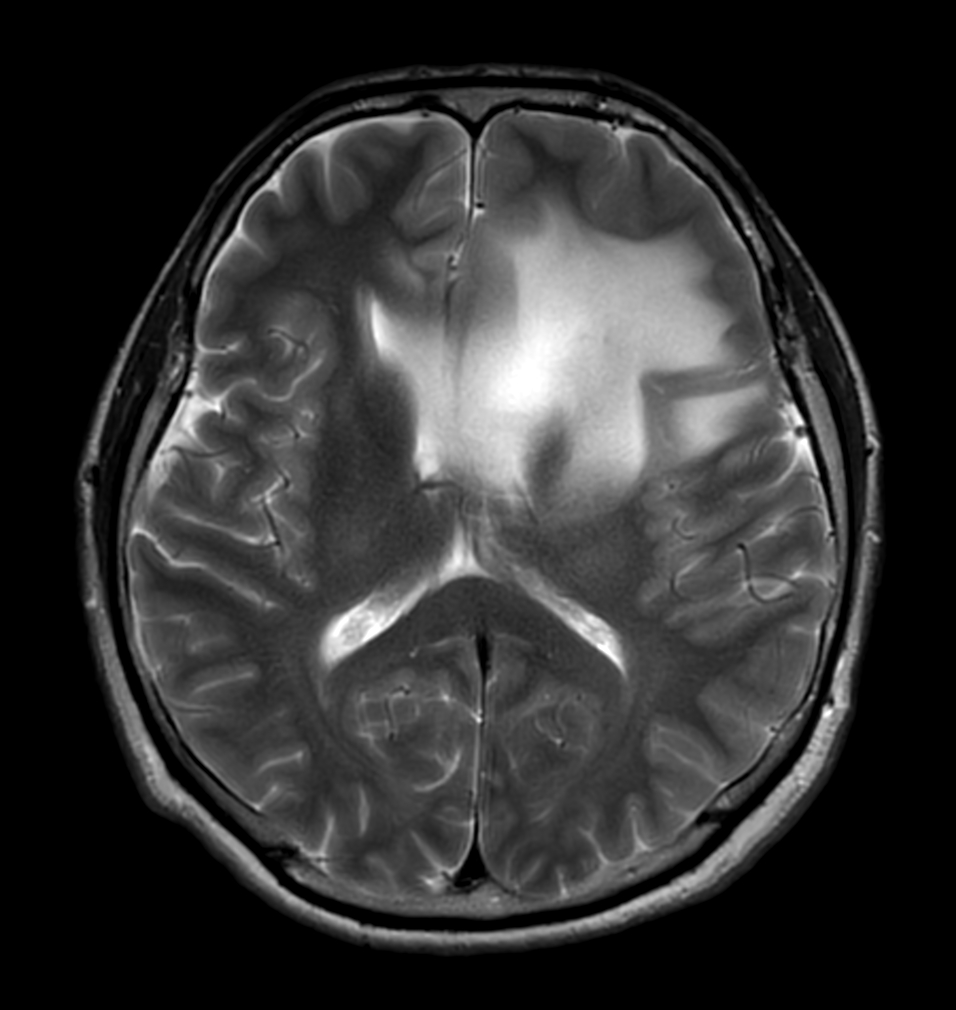

T2w TSE - MultiVane XD